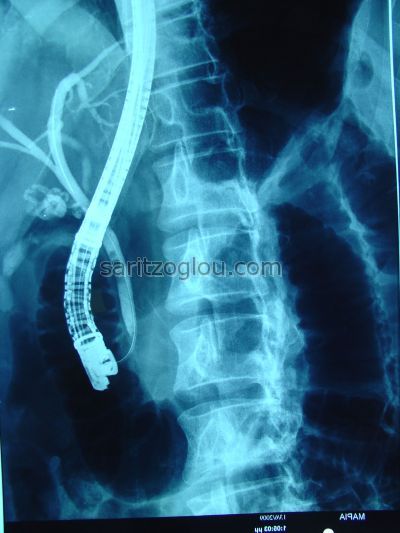

Χοληδοχολιθίαση. Έγινε λιθοτριψία και τοποθέτηση pig-tail stent Aαπεικόνιση υπολοιπόμενου λίθου εντός του πόρου.